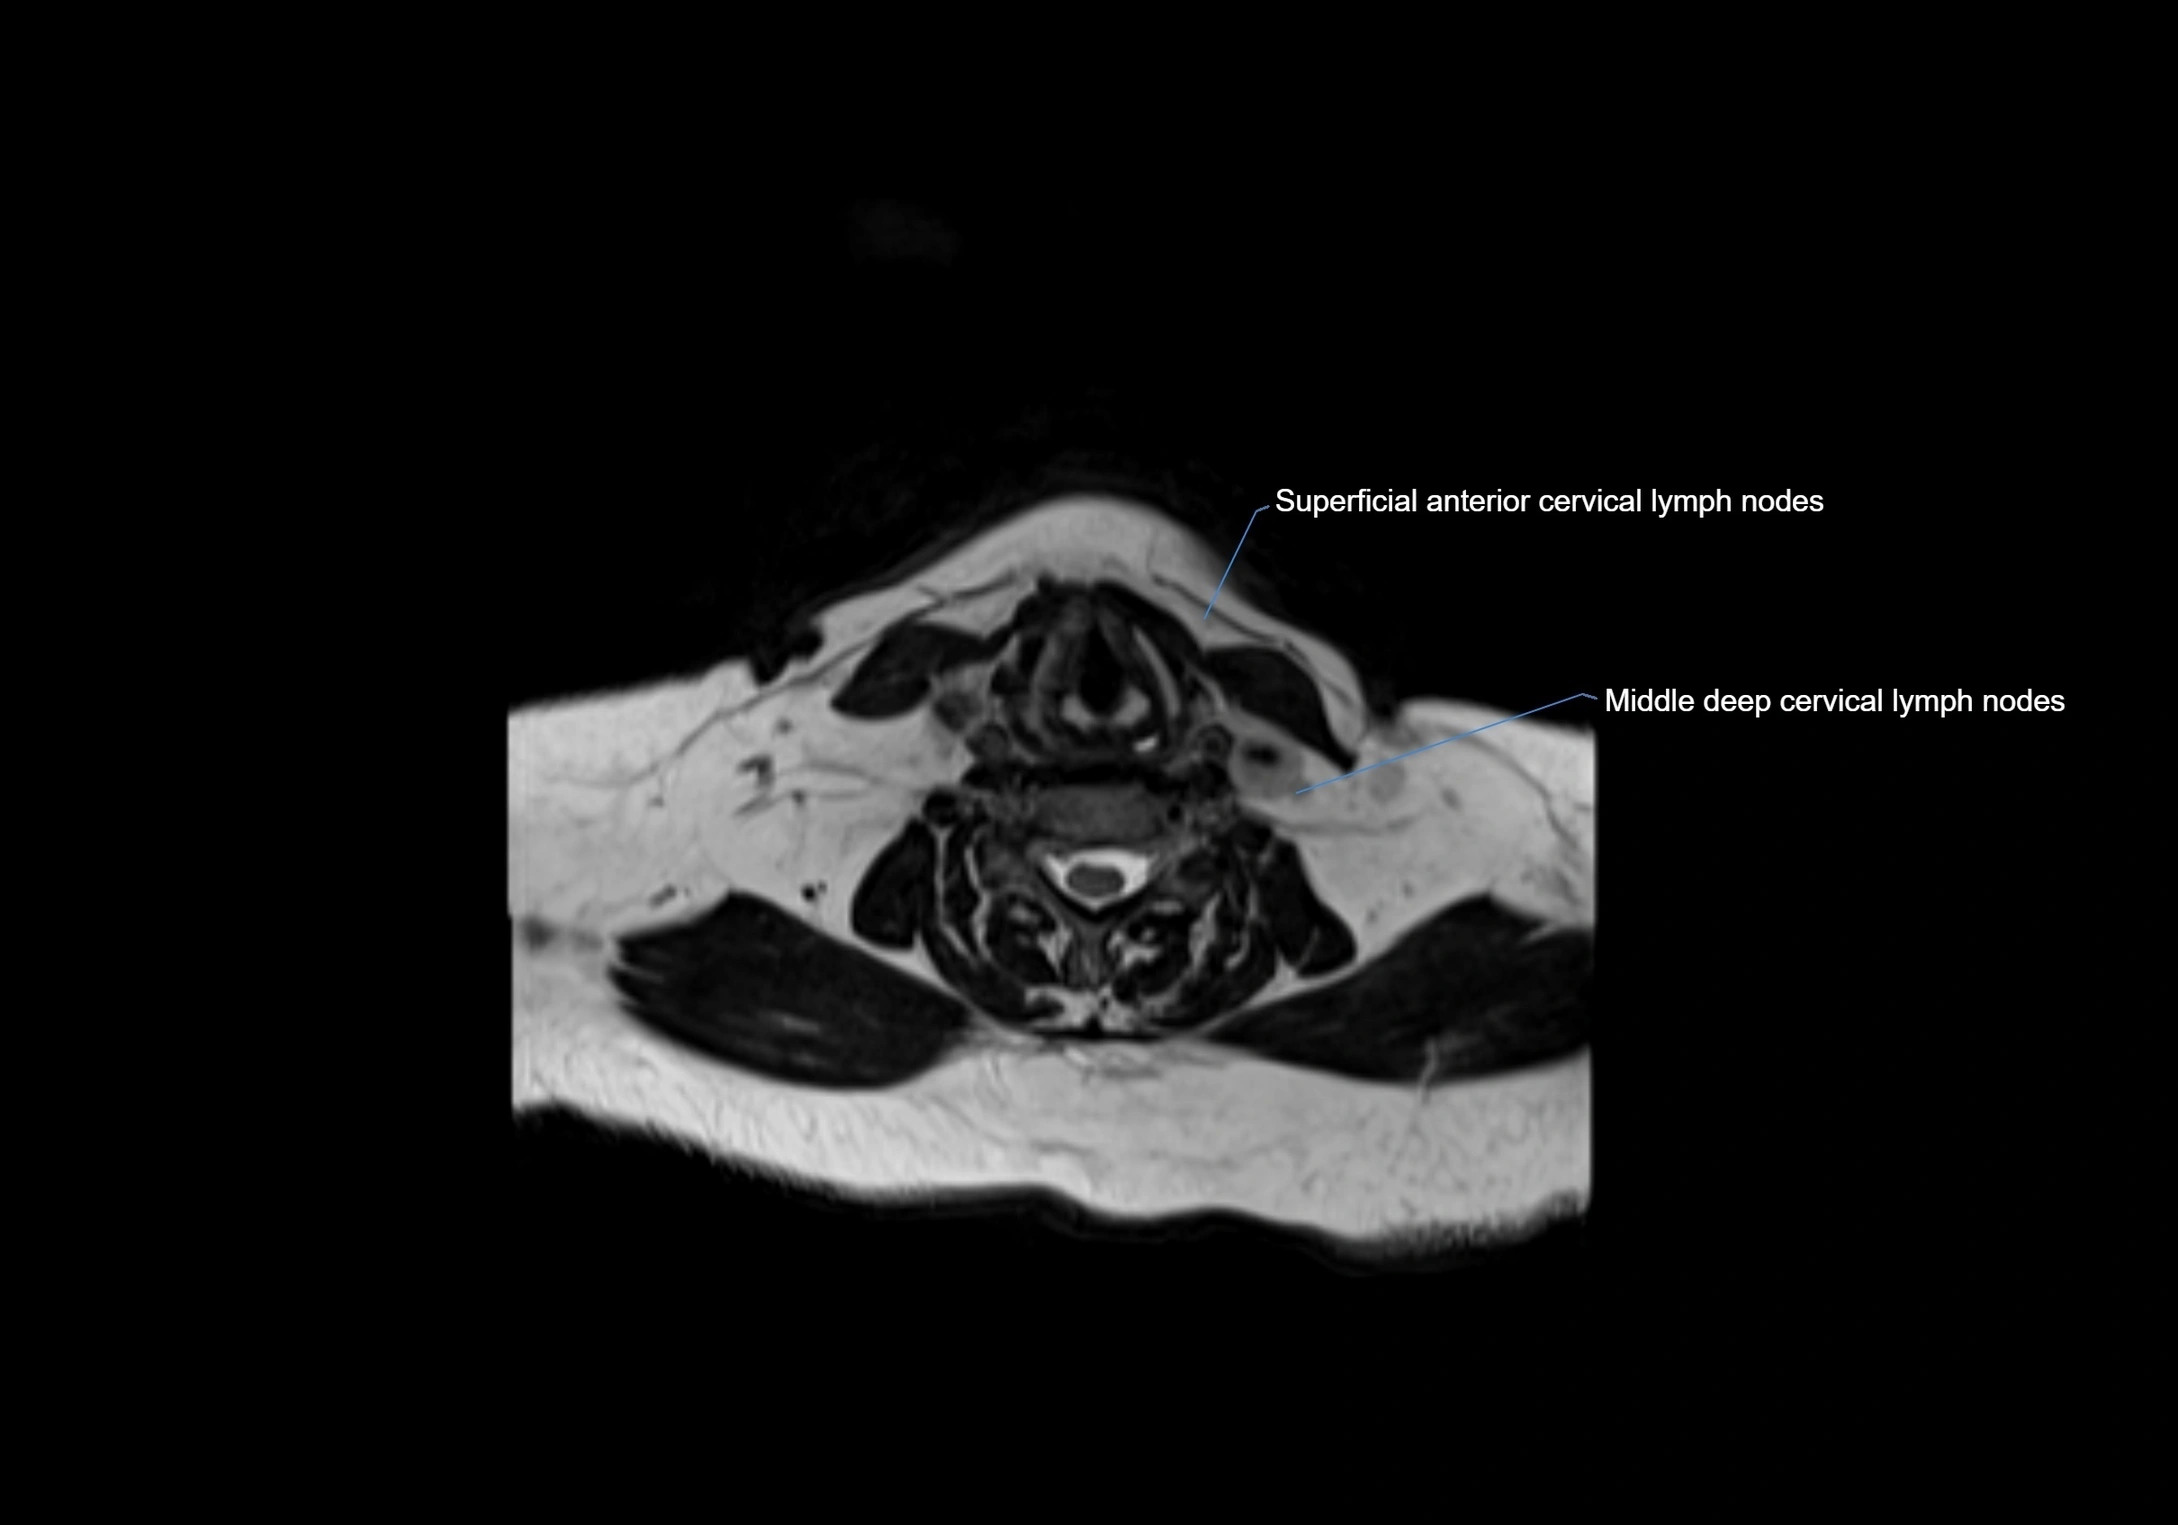

MRI images

image